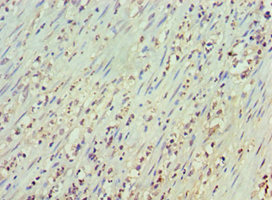

IHC

新闻图片12

MS4A1 Antibody

(CSB-PA015007DSR2HU)

新闻图片13

新闻图片14

MS4A1 Monoclonal Antibody

(CSB-MA000204)